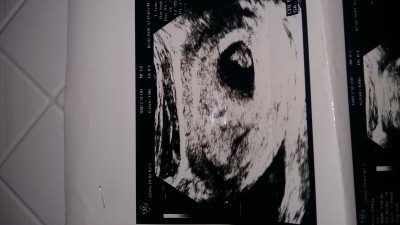

Arkadsimin kizlar 6 haftalik

Kız bebe daha belli değil ki, içimden kız geçti

Daha çok küçük ama erkek gibi

Kese kız gibi hayırlı evlat olsun inşallah